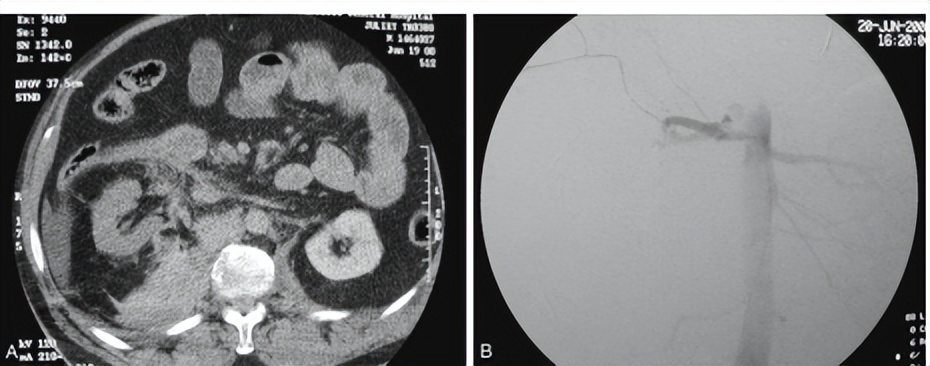

(A)CT显示右肾动脉血栓形成造影剂显示不良与右侧内侧肾和右肾外周软组织损伤比较肾动脉结构异常。(B)血管造影显示右肾动脉损伤后血栓形成。

5.肾动脉损伤:钝性肾损伤造成的肾动脉血栓形成多见于减速伤,动脉内膜下弹力纤维破裂继发血栓形成堵塞血管,表现为肾缺血。对于单侧者行动脉血管重建很难使患肾恢复功能,如果是双侧者建议迅速肾动脉重建以避免可能的透析治疗。